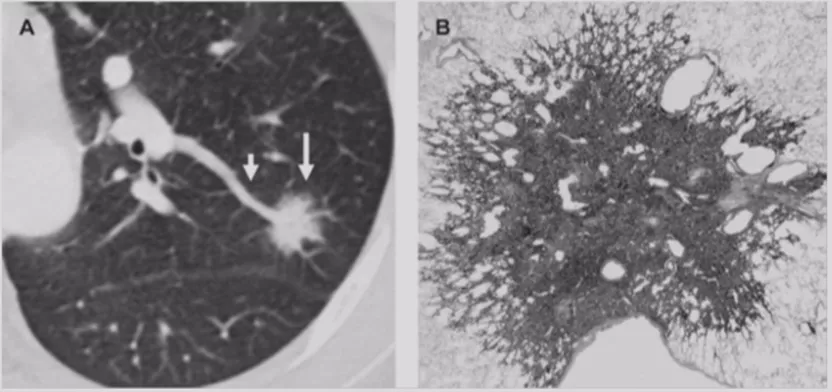

肺腺癌

首先是肺癌。现在肺腺癌的发病率在肺癌中占比较高,它可以表现为GGO,可以是一个癌前病变,我们叫不典型腺瘤癌增生或者是原位癌,这个时候如果是原位癌,手术效果是相当理想的。一旦它出现实性成分,有可能就变成一个微浸润癌。随着实性成分不断增加,恶性成分就越来越多,当它完全变成实性的,就发展为一个浸润癌。这样的病人大家基本上都能诊断清楚,我们应该争取在恶性程度增高这个阶段之前把病人诊断清楚,这样5年乃至10年的生存率都非常高。因此,肺腺癌结节的特征还是非常不一样的。

微浸润性腺癌(MIA)

进一步发展里面出现实性成分,或者结节的大小逐渐增大。微浸润性腺癌多位于肺外周,多为单发,一般<2cm,一般到了2cm就更严重了。最主要的是影像学多表现为边界清楚的部分实性结节,GGO比例>50%,实性成分多≤5mm。组织学上肿瘤细胞贴壁生长为主,多为非粘液型。此时要考虑微浸润的问题,这个时候手术效果还是非常好的。